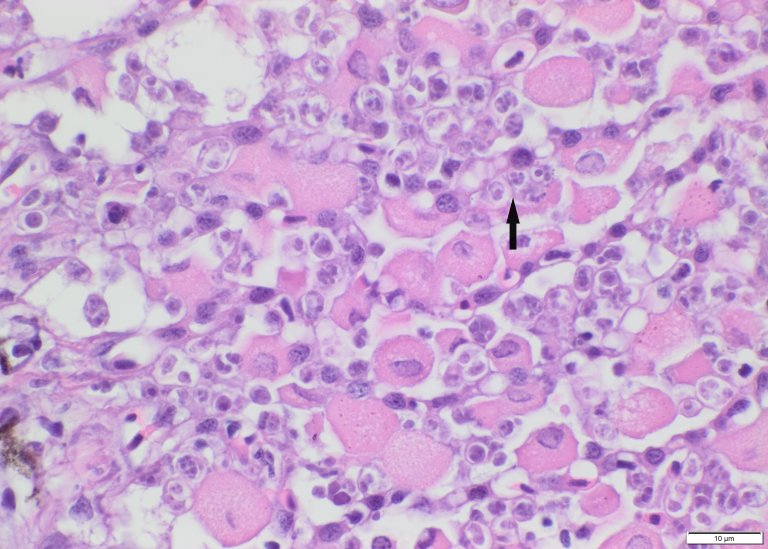

Pseudobrankier hos laks med den flercellede parasitten Parvicapsula pseudobranchicola (pil). Foto: Toni Erkinharju, Veterinærinstituttet

Det endelige målet for infeksjonen i fisk er at det blir dannet sporer som kan gå ut av fisken og infisere hovedverten. Organet der disse myxosporane blir dannet kalles målorgan og for P. pseudobranchicola er målorganet vist å være pseudobrankiene, derav det latinske navnet. Myxosporane vil etter hvert fylle opp store deler av vevet i pseudobrankien og gjøre stor skade.